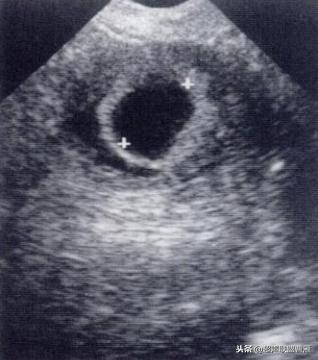

正常早孕卵黄囊声像图

早孕 胚芽 卵黄囊

5周+ 、6周+ 声像图

· 正常情况下,卵黄囊中央表现为无回声,周边为厚薄均一、边界清晰的环形高回声。

· 正常卵黄囊内径一般在3-5mm,妊娠第5-10周逐渐增大,而10周后逐渐减小,一般12周前消失。